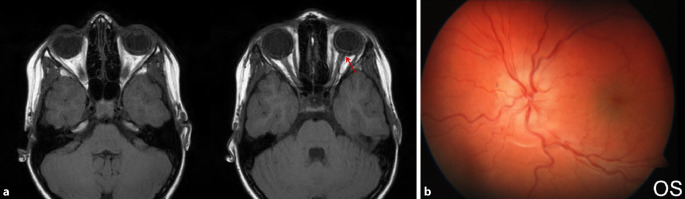

Papillenödem, Stauungspapille e vacuo: Durch den im Vergleich zum Liquordruck erniedrigten Augeninnendruck entsteht das Bild einer Stauungspapille (Abb. 7a, b).

Die Diagnostik bei persistierender Bulbushypotonie umfasst bei inzwischen verschlossener Wunde die Visustestung mit und ohne Korrektur beider Augen, die Bestimmung der Akkommodationsbreite, die Spaltlampenbiomikroskopie, die Seidel-Probe, die Gonioskopie [6, 12, 28, 36], die Fundoskopie und Intraokulardruckmessung beider Augen, Achslängenmessung beidseits, Ultraschalluntersuchung, Ultraschallbiomikroskopie (UBM) bzw. Vorderabschnitts-OCT (optische Kohärenztomographie). Mitunter wird unnötigerweise eine zerebrale Magnetresonanztomographie(MRT)- oder Computertomographie(CT)-Untersuchung aufgrund der Papillenschwellung durchgeführt (Abb. 7a), um eine zerebrale Raumforderung auszuschließen, dies liegt jedoch eher an der fehlenden Diagnosestellung einer Stauungspapille e vacuo bei Zyklodialyse oder Bulbushypotonie. In jedem Fall sollte die augenärztliche Diagnostik abgeschlossen sein, bevor man eine aufwendige Bildgebung initiiert (eine Ausnahme stellen komplexe Orbita-Augen-Verletzungen oder der Ausschluss eines intraokularen Fremdkörpers dar). Im Rahmen traumatologischer Fragestellungen

traumatologischer Fragestellungen

hat die CT gegenüber der MRT den deutlich höheren Stellenwert, da hierdurch keine Gefährdung bei metallischen intraokularen Fremdkörpern vorliegt und zudem knöcherne Strukturen besser darstellbar sind.